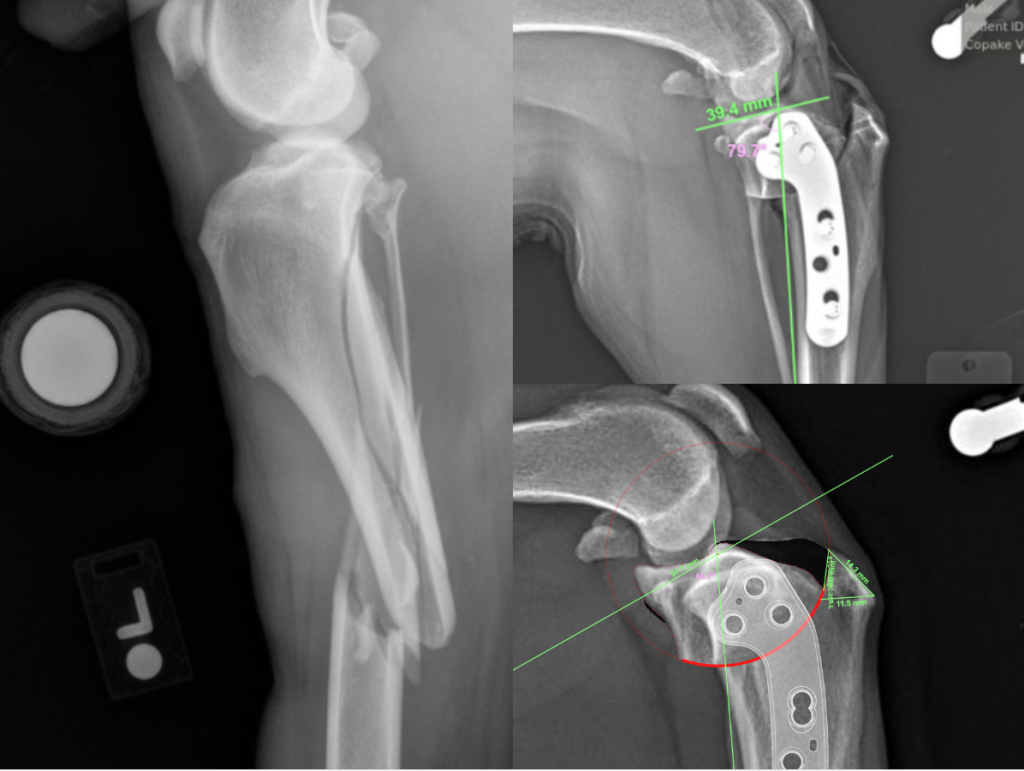

- Internal fixation of fractures with plates and screws as well as with pin and cerclage wires

- Dr. Hotaling is completing training on Tibial Plateau Leveling Osteotomy (TPLO) and hopes to be offering it to patients by the Fall of 2026.